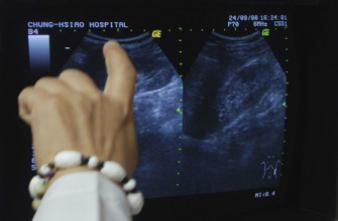

- Chiang Ying-ying/AP/SIPA

Les traitements des calculs rénaux sont peu risqués, mais leurs complications coûtent cher. Dans un cas sur sept, une opération en ambulatoire débouche sur une seconde visite à l’hôpital, imprévue cette fois. C’est ce que conclut une équipe de l’université Duke (Caroline du Nord, Etats-Unis), ce 28 avril dans Surgery.

Jusqu’à 30 000 $

Les chercheurs ont passé en revue les dossiers de 93 000 patients traités pour des calculs rénaux. La plupart du temps, les opérations sont peu invasives. Les trois plus courantes sont une lithotripsie par ondes de choc (fragmentation des calculs, ensuite évacués naturellement), une urétroscopie (extraction via l’urètre) ou une néphrolithotomie percutanée (fragmentation des calculs puis extraction via la paroi lombaire). Ces opérations sont réalisées en chirurgie ambulatoire, ce qui représente une économie.

Mais les complications liées à un traitement des calculs rénaux font grimper la facture, pour le patient comme le système de santé. Selon le type d’opération et les complications qui en découlent, une seule visite imprévue peut représenter jusqu’à 30 000 $ (21 600 €) ! « Nos résultats fournissent un bon point de départ pour comprendre pourquoi ces complications surviennent, et comment elles pourraient être prévenues », se félicite le Dr Charles Scales Jr., principal auteur de l’étude.

Economiser des surcoûts évitables

Les conclusions de l’étude sont éloquentes. Les hôpitaux qui pratiquent le plus d’opérations en traitement des calculs rénaux sont aussi ceux qui observent le moins de complications. Quand des complications surviennent, elles suivent moins souvent une lithotripsie par ondes de choc (12% des patients). Mais elles coûtent aussi très cher : une visite aux urgences représente en moyenne 32 000 $ (23 000 €). Après une néphrolithotomie, les complications nécessitent en moyenne une dépense de 47 000 $ (33 900 €).

Ces événements ne sont pas très fréquents, mais les patients n’en sont pas toujours conscients, note le Dr Scales : « Du point de vue du patient, une visite imprévue aux urgences ou une admission à l’hôpital après une opération en ambulatoire à faible risque est un événement de taille », souligne-t-il. D’ailleurs, le coût des complications pose souvent problème. « Les calculs rénaux sont atrocement douloureux et affectent surtout les actifs. Ces patients ne subissent pas seulement le coût du traitement, mais aussi les difficultés financières liées à un arrêt de travail », signale le Dr Scales. En comprenant comment ou pourquoi ces événements surviennent, il serait possible de réaliser de larges économies : pour le patient, qui débourse des sommes supplémentaires, mais aussi pour le système de santé, qui rembourse ces dépenses, et la société qui ne pâtit plus de l’absentéisme.